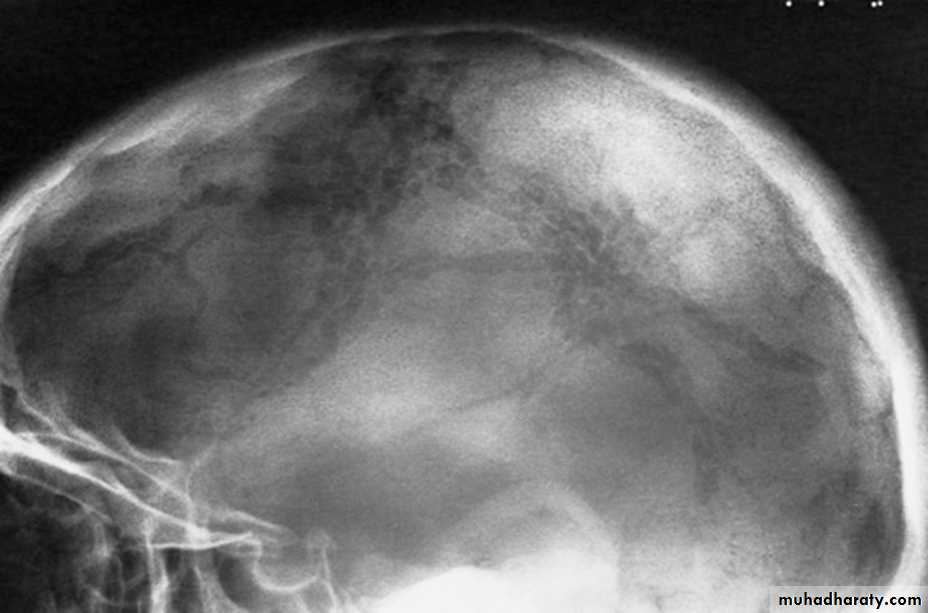

Skull X-rayBony configuration and shape

Bone densityAny Lytic lesion

Any calcification

Diploë, pituitary fossa, paranasal sinuses, orbits

The normal pituitary fossa as shown in a lateral skull film can vary considerably in size. Normal figures are (length of 11-16 mm and a depth of 8-12 mm)• Pineal